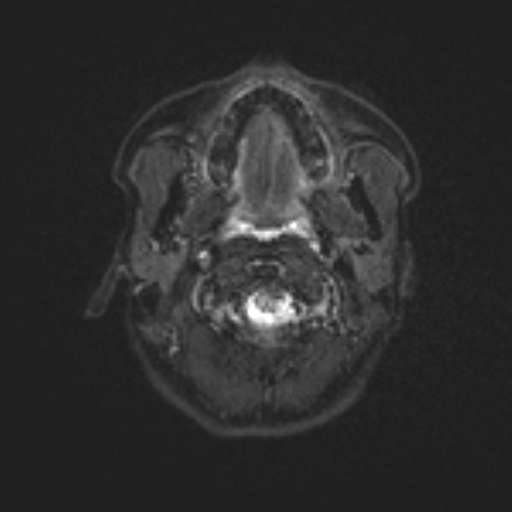

Nome Paziente: MACARI^NATALIA Identificativo: VSM_01222260 Data di Nascita: 07-06-1995 Sesso: F

Esame: RM ENCEFALO MDC del 24-03-2026